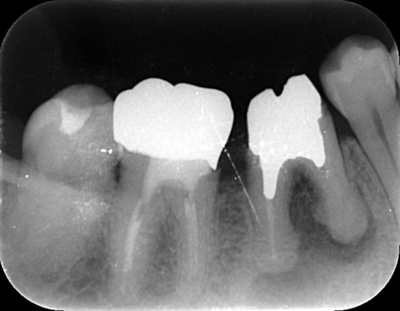

2022.7.9 経過観察後

口腔内写真

レントゲン写真

根管治療後3ヶ月です。根のまわりの骨がやや白くなってきているのがわかります。だんだん骨の添加がみられている証拠になります。

ここまで治癒していればかぶせ物をかぶせても問題ないと判断しました。